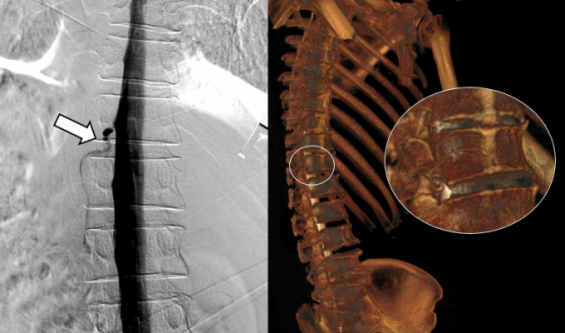

- 전 자발성 두개내 저하증이 의심됐으나 척추 MRI와 단순 척수 조영술 검사에서 전부 정상 소견을 보였다. 환자 본인의 혈액으로 뇌척수액 누출 위치를 막는 자가혈액패취술 등을 시행해도 환자들의 증상은 호전되지 않았다. 뇌 압력이 낮아져 뇌를 감싸는 경막 내부와 정맥을 이어주는 ... ...